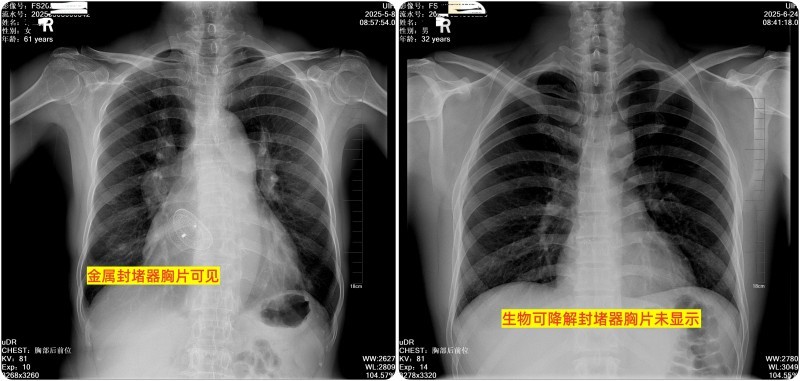

图片3:金属封堵器与可降解封堵器对比